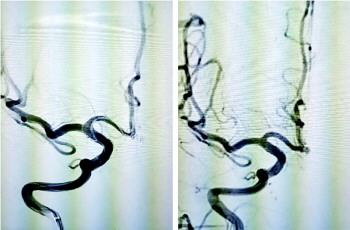

当日下午2点,手术开始。杜福宏在患者大腿根部切开一个1毫米的切口,先行脑血管造影,与副主任医师宋良鹏、主治医师郑德伟术中再进一步讨论后,决定行支架辅助弹簧圈栓塞术。术中,杜福宏动作沉稳、精准施术,经过各种导管,支架半释放,小心翼翼地填入4个弹簧圈致密栓塞瘤体,历经3小时,造影显示脑血管通畅,瘤体不显影,达到预期良好效果,手术圆满成功。据悉,弹簧圈是专门栓塞动脉瘤的材料,经很细微导管顺血管送入瘤内后成型,起到填充作用,而且会加快动脉瘤内的血液凝固形成血栓,因此术后血液无法流进动脉瘤内,动脉瘤再次破裂的风险大大减少。

(手术前后血管对比图)